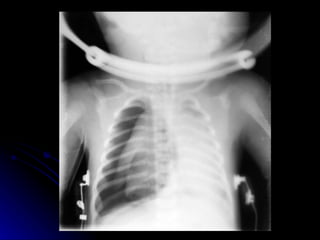

Pneumothorax Clinical:- May be asymptomatic May be life threatening Sudden deterioration in gas exchange Poor colour Hypotension and tachycardia Unilateral overexpanded thorax

Pneumothorax - aetiology Uneven alveolar ventilation Air trapping and high pressure swings Tracking of air from pulmonary interstitial emphysema

Pneumothorax - predisposing factors Spontaneous in 1% of all babies Increases with mechanical ventilation Increased x 4 with HMD Increased x 16 with CPAP Increased x 34 with IPPV

Pneumothorax - Treatment None if asymptomatic Nitrogen washout technique - high FiO2 in term babies only Chest drain if tension pneumothorax or on mechanical ventilation Emergency needle thoracocentesis

Pneumothorax Clinical:- Maybe asymptomatic May be life threatening Sudden deterioration in gas exchange Poor colour Hypotension and tachycardia Unilateral overexpanded thorax

Pneumothorax - aetiologyUneven alveolar ventilation Air trapping and high pressure swings Tracking of air from pulmonary interstitial emphysema

Pneumothorax - predisposingfactors Spontaneous in 1% of all babies Increases with mechanical ventilation Increased x 4 with HMD Increased x 16 with CPAP Increased x 34 with IPPV

Pneumothorax - TreatmentNone if asymptomatic Nitrogen washout technique - high FiO2 in term babies only Chest drain if tension pneumothorax or on mechanical ventilation Emergency needle thoracocentesis